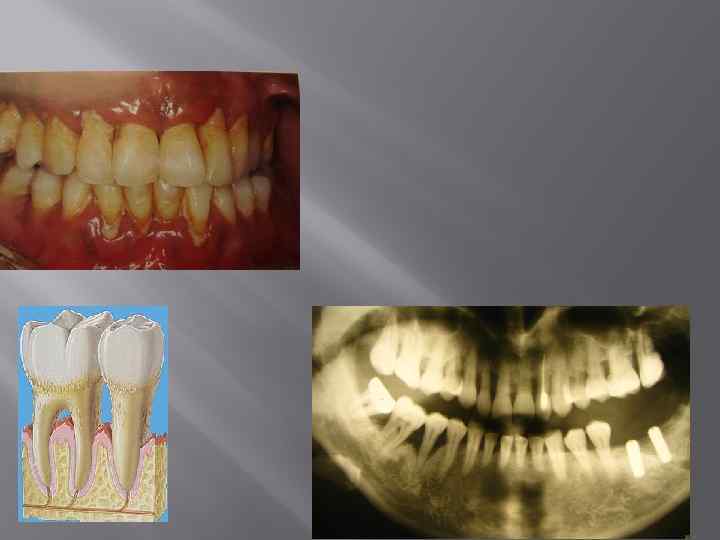

Клинические признаки заболеваний пародонта Хронический генерализованный пародонтит легкой степени: Зубо-десневой карман -3, 5 -4 мм Серозный эксудат Кровоточивость -1 -2 балла Подвижность зубов – I степени Рентгенологически определяется резорбция костной ткани равномерного вертикального типа до ⅓ длины корней Дефекты зон фуркаций I класса

Клинические признаки заболеваний пародонта Хронический генерализованный пародонтит средней степени Зубо-десневой карман -5 -6 мм Серозно-гнойный эксудат, при обострении –гнойный с рецессией 1 класса по Миллеру Кровоточивость -3 -4 балла Подвижность зубов – I –II степени Рентгенологически выявляют вертикальную неравномерную резорбцию костной ткани альвеолярных отростков Зоны фуркаций обнажены

Клинические признаки заболеваний пародонта Хронический генерализованный пародонтит тяжелой степени Зубо-десневой карман – более 5 -6 мм Серозно-гнойный эксудат, при обострении гнойный Кровоточивость -2 -3 -4 балла Подвижность зубов – III степени Значительное обнажение корней зубов более ½ длины корней с туннелеобразным входом в зону фуркации и резорбцией межкорневой и межзубной перегородки более половины, ⅔ длины корней